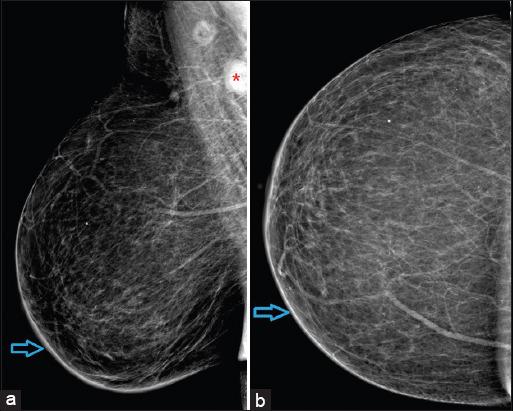

A total of eight cases were identified, out of which seven were females. The most common presentation consisted of the presence of metastatic nodules which were seen in 62.5% (five out of eight) of the patients. Other features consisted of erythematous or plaque-like skin thickening on clinical examination, increased density with indistinct margins seen on a mammogram and diffuse oedematous changes in the skin with small irregular mass or infiltration into subcutaneous tissues were visualised on ultrasound and CT studies.